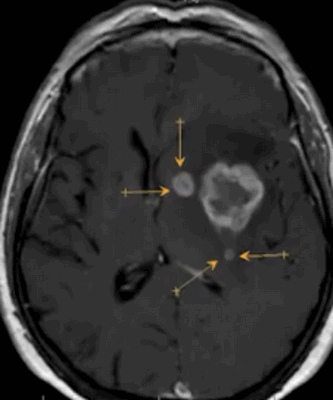

Метастазы в головном мозге на постконтрастном изображении (указаны стрелками)

Опухоль головного мозга на МРТ с отсевами (указаны стрелками)